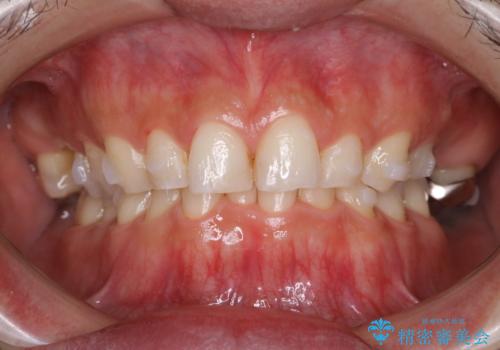

インビザラインでのマウスピース矯正中にPMTCでステインの除去

- インビザラインでの矯正治療中に着色を取るクリーニンングも行いたいとのことでした。PMTC30分コースを行いました。

矯正治療中は虫歯や歯周病リスクが高くなることがあります。

インビザライン矯正治療はマウスピースを長時間使用するため、歯石や汚れ・着色などが付着したままだと、フィットが悪くなったり、口臭が強く出たりする原因につながることもあります。